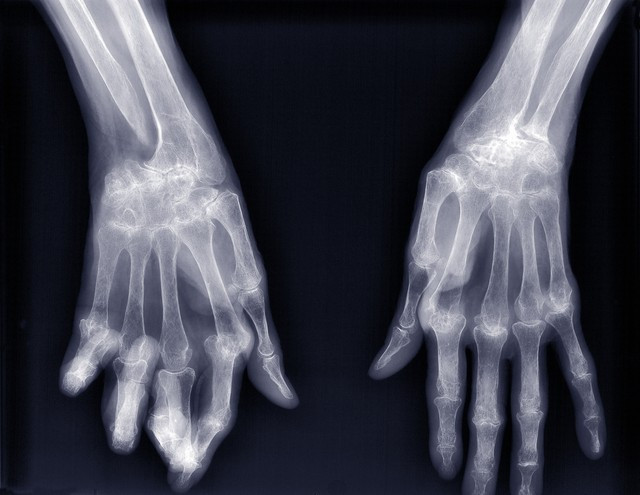

此外,患类风湿性要害炎、躁郁症和精神离别症的风险也在进化经过中有所着落。